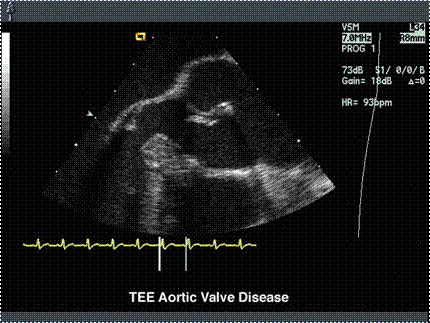

M - mode: ecou de separare diastolic, flutter valvular mitral, > DTSVS > 55 mm

2D - mode

- valvele aortice nu se inchid in diastola,

- anomalii congenitale (bicuspidia),

- rupturi, vegetatii,

- flux turbulent (Doppler) cu velocitate crescuta,

- grade 1-4 in raport cu lungimea jetului.